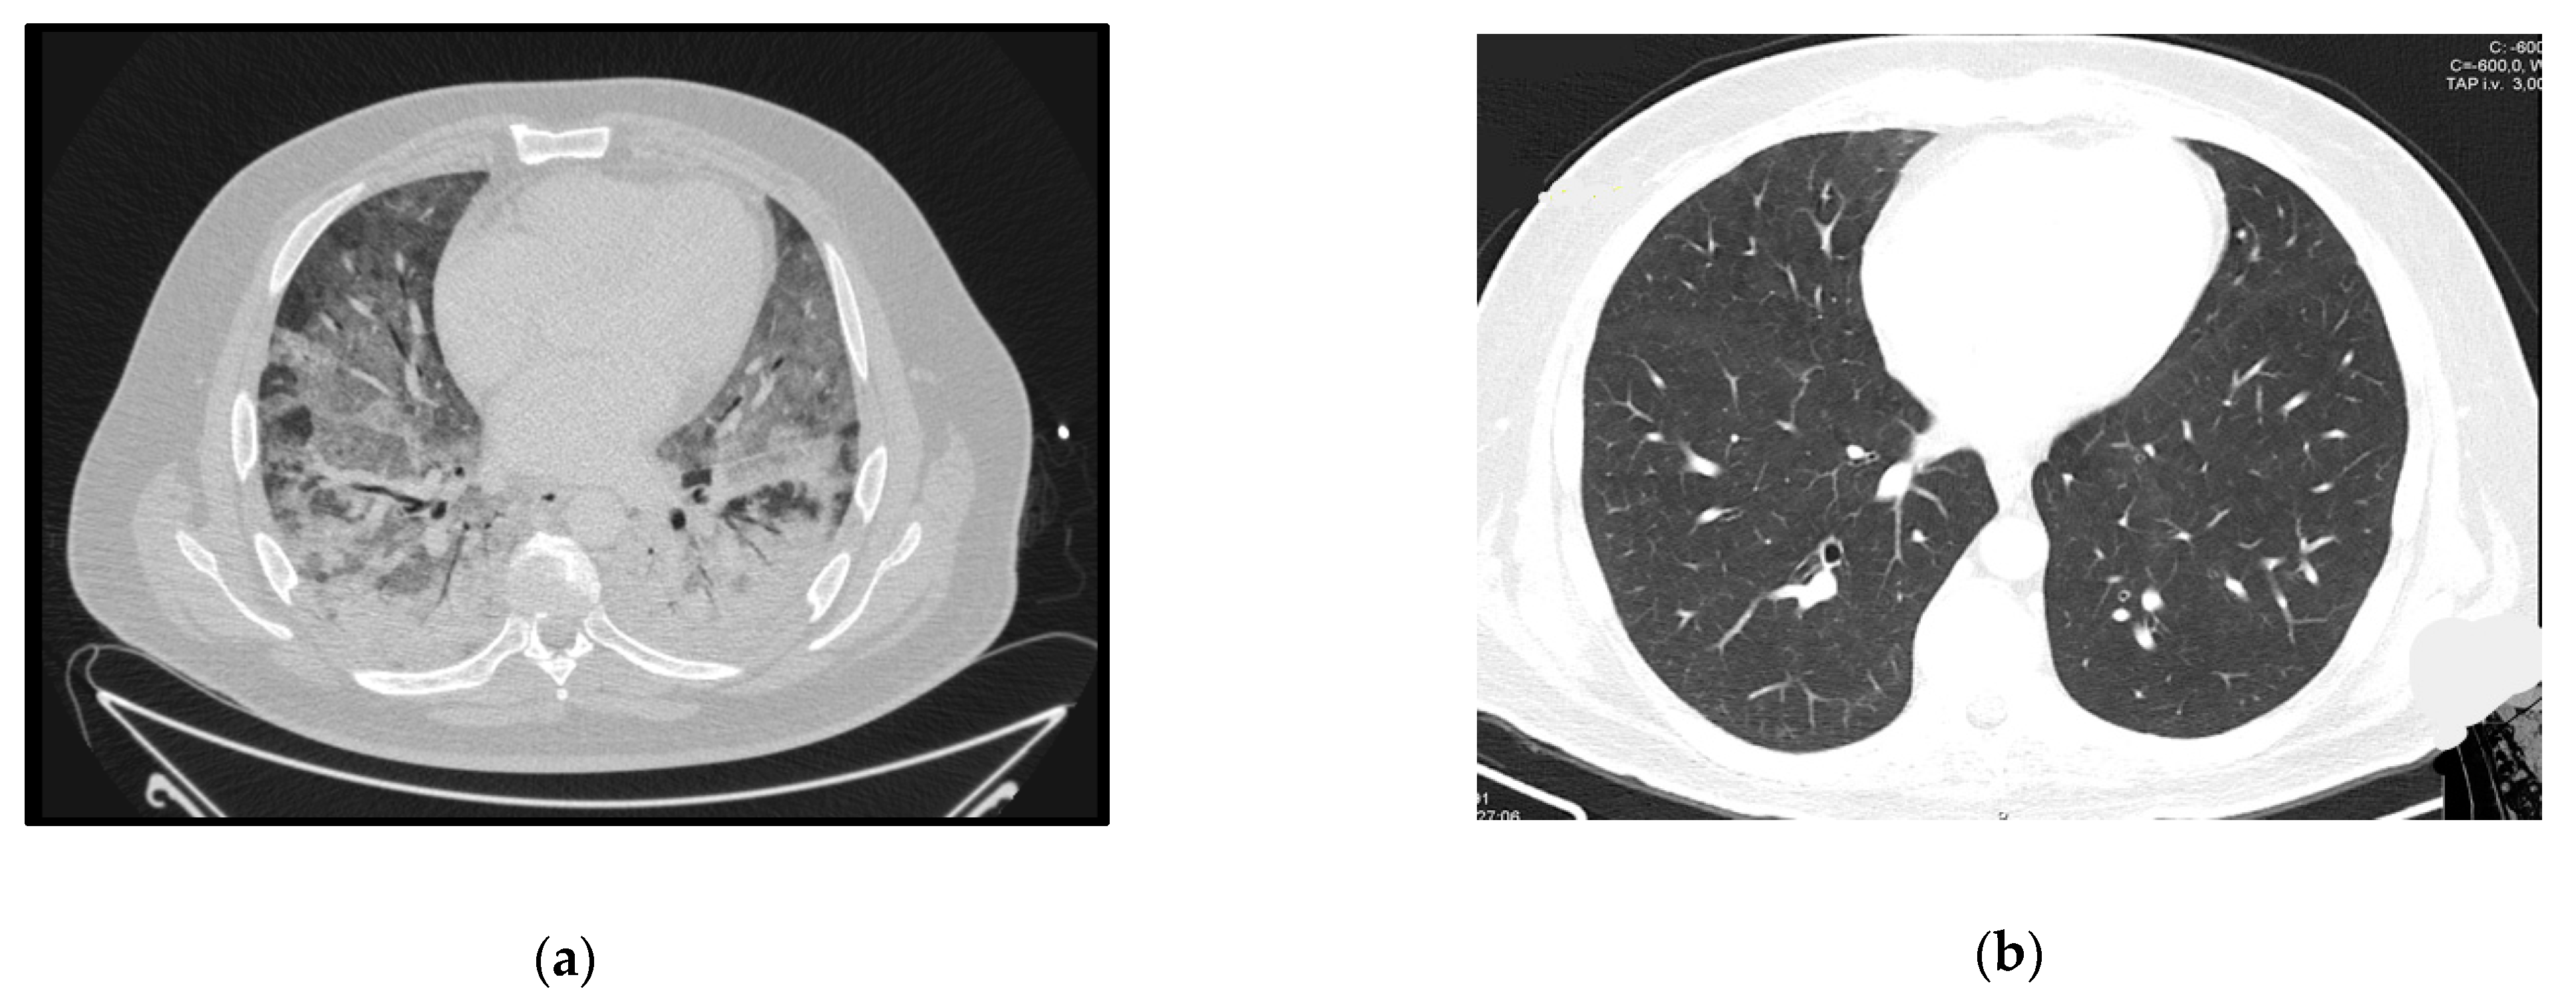

A 36-year-old male, overweight and with HIV infection diagnosed in 2009, with poor adherence to appointments and complete discontinuation of ART in the three months before admission.

The patient presented at the ER with a 3-week history of worsening cough, dyspnea, and fever. Initial assessment showed hypoxia, fever (39 °C), elevated CRP, 6 CD4+ lymphocytes/mm3 and several ground glass opacities on thoracic CT-scan (Figure 4a). He started empirical treatment with TMP-SMX plus corticosteroids at the recommended PJP treatment dosage and was admitted to the ward. The need for oxygen support increased in the next few hours and the patient responded poorly to HFOT. Twenty-four hours later he was admitted to the ICU and VV-ECMO was started. No tracheal intubation was performed. PJP was confirmed by positive immunofluorescence in BAL.

Figure 4.

Case 4 thoracic CT-scan at diagnosis (a) and follow-up (b).

After 9 days of ECMO support the patient became delirious and agitated, which caused flow problems in the extracorporeal circuit and eventually led to the need for sedation and subsequent intubation. He completed 21 days of treatment, initially with TMP-SMX, then changed to atovaquone plus primaquine due to hematologic toxicity. ECMO support was maintained for 26 days.

He was transferred to the ward for rehabilitation after 37 days of ICU stay, and already on ART. The follow-up CT-scan can be seen in Figure 4b.